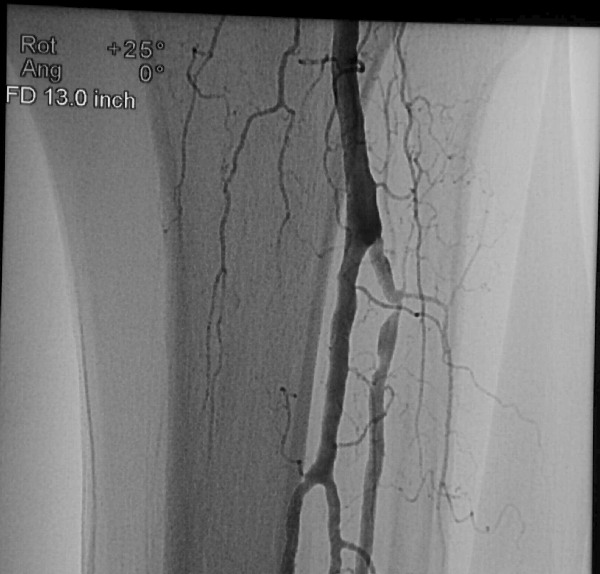

After completing angiogram procedures, surgeons performed an antegrade puncture of the left common femoral artery and placed a 6-Fr sidearm sheath with its tip in the proximal superficial femoral artery. A repeat diagnostic study confirmed the previous findings. The team subsequently used a 4-Fr Berenstein catheter with glide coating (Boston Scientific) loaded with a .014-inch guidewire (Sparta/Core 14, Guidant Corp.) to catheterize the anterior tibial artery and cross the stenosis. The vascular surgeons performed cryoplasty therapy with a 3 mm by 20 mm PolarCath Peripheral System balloon (CryoVascular Systems, Inc.). A post-op control angiogram showed excellent results with a less than 10 percent residual stenosis and no angiographic evidence of dissection. The vascular surgeons proceeded to turn their attention toward the occluded segment of the anterior tibial artery. They advanced the 4-Fr glide Berenstein catheter across the aforementioned treated segment and placed the tip of the catheter just above the occluded portion of the artery. After injecting contrast, the surgeons documented reconstitution of the post-obstructed anterior tibial artery. The surgical team crossed the obstructed segment with a 0.035-inch straight, stiff Glidewire (Boston Scientific), advanced the catheter across the obstruction and confirmed its intraluminal position with a contrast injection. Using the 3.0 mm balloon, they treated the obstructed segment with cryoplasty therapy. A post-op control angiogram disclosed minimal residual stenosis and no vessel wall dissection. There was no evidence of distal embolization of plaque fragments. The vascular surgeons advanced the 0.014 inch guidewire through the balloon catheter and crossed the stenosis of the dorsalis pedis artery again, utilizing a roadmap technique. They treated the stenosis of the dorsalis pedis artery at and below the ankle with a 2.5 mm by 20 mm CryoPlasty balloon. A post-op control angiogram showed significant improvement in the diameter of the dorsalis pedis artery with a focal area of spasm at its mid-portion. The patient tolerated the procedure well and the multidisciplinary team noted a strong, palpable dorsalis pedis pulse after the procedure.